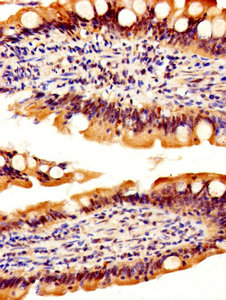

IHC image of CSB-PA019548EA01HU diluted at 1:500 and staining in paraffin-embedded human small intestine tissue performed on a Leica BondTM system. After dewaxing and hydration, antigen retrieval was mediated by high pressure in a citrate buffer (pH 6.0). Section was blocked with 10% normal goat serum 30min at RT. Then primary antibody (1% BSA) was incubated at 4°C overnight. The primary is detected by a biotinylated secondary antibody and visualized using an HRP conjugated SP system.